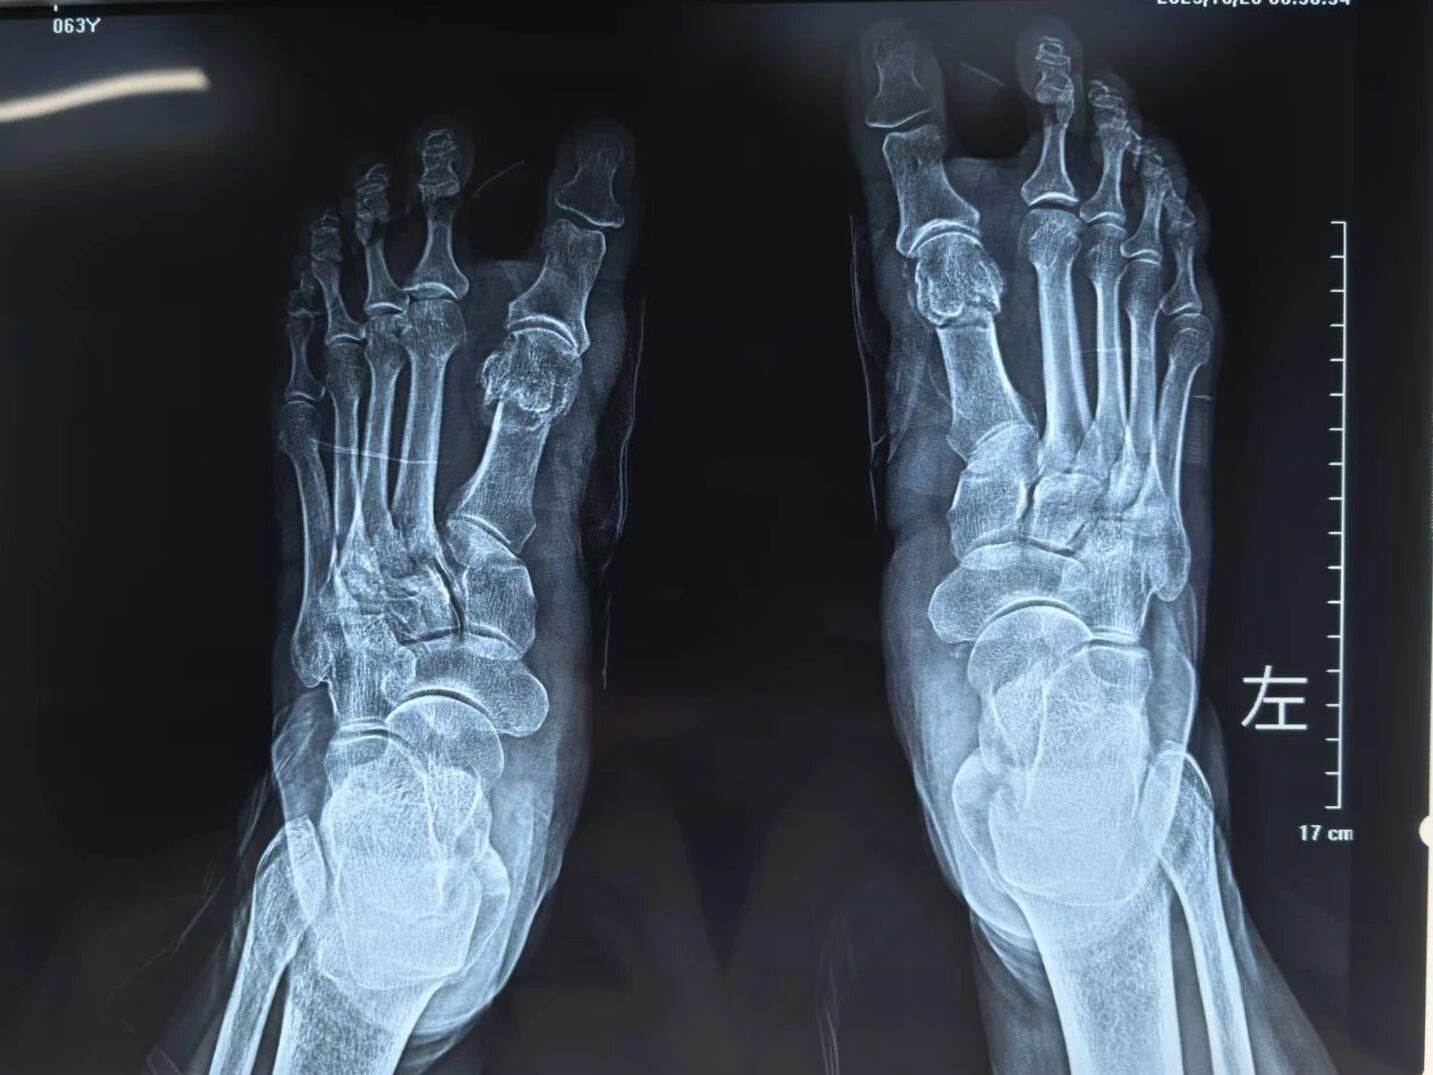

▲术后

▲术前